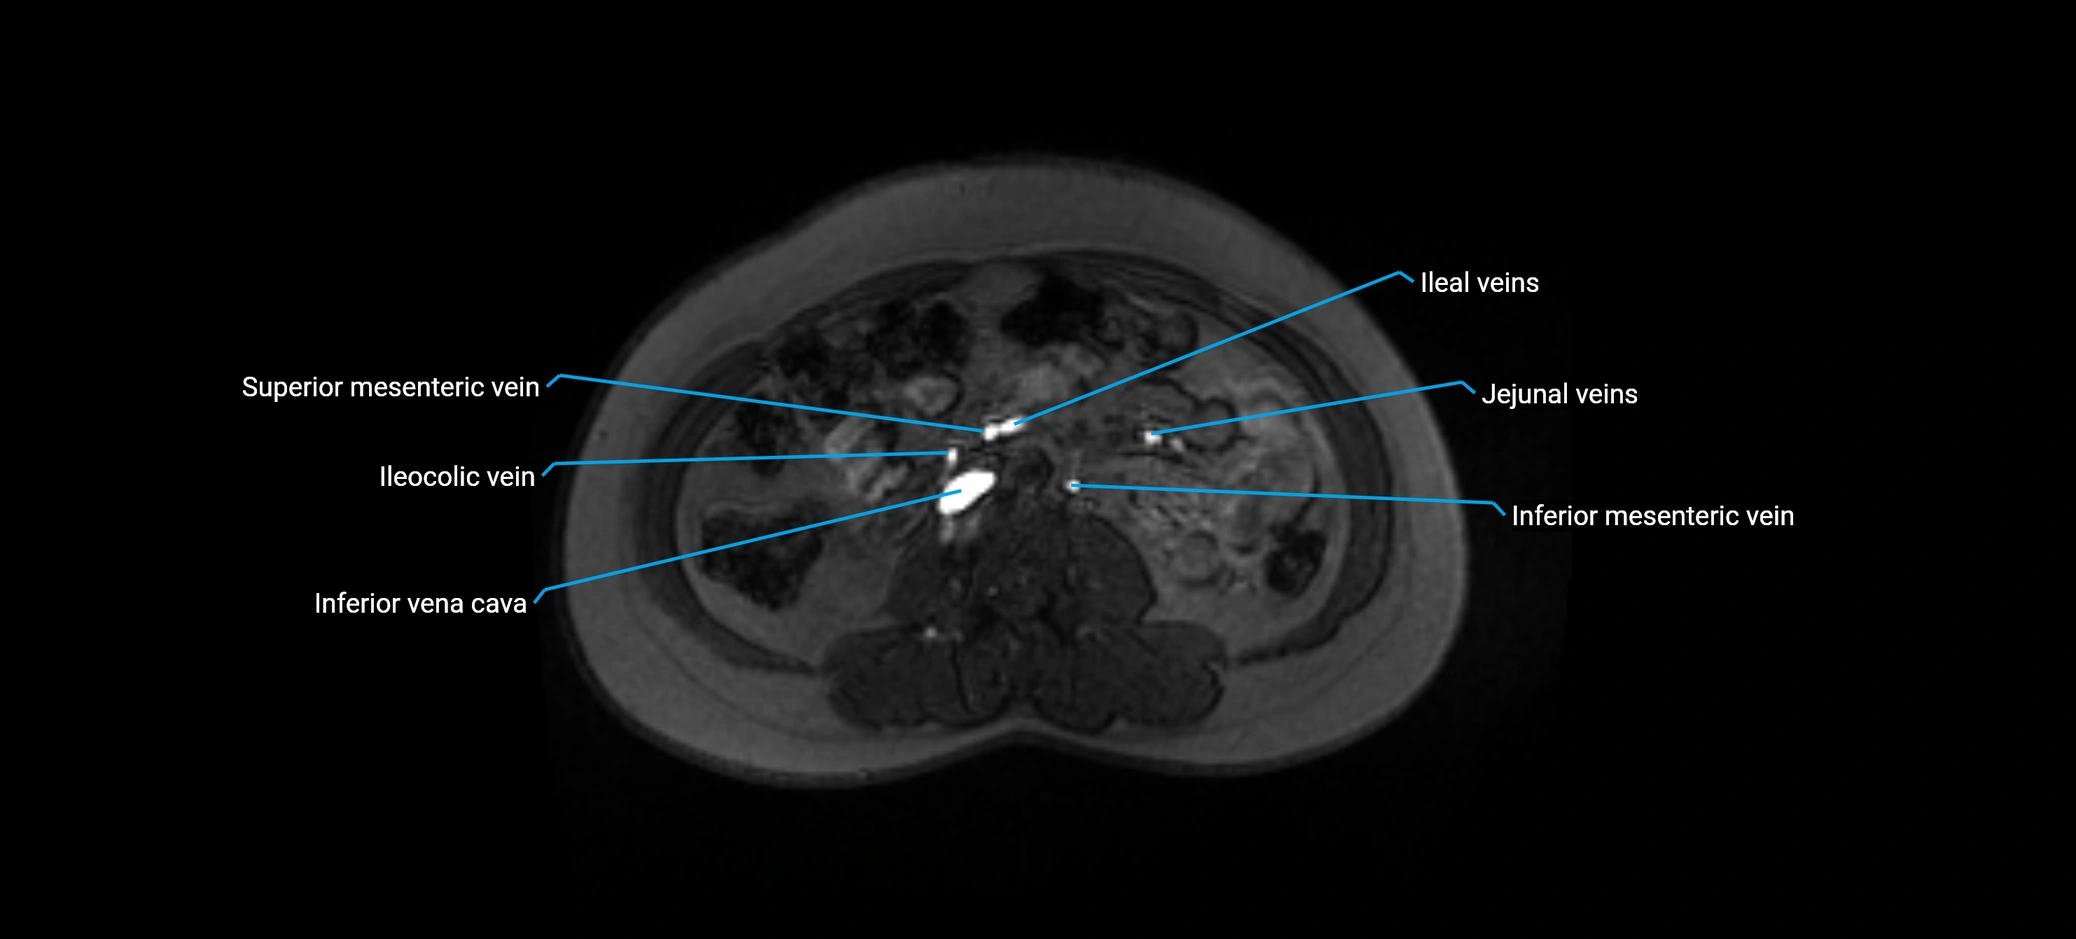

MRI image

image